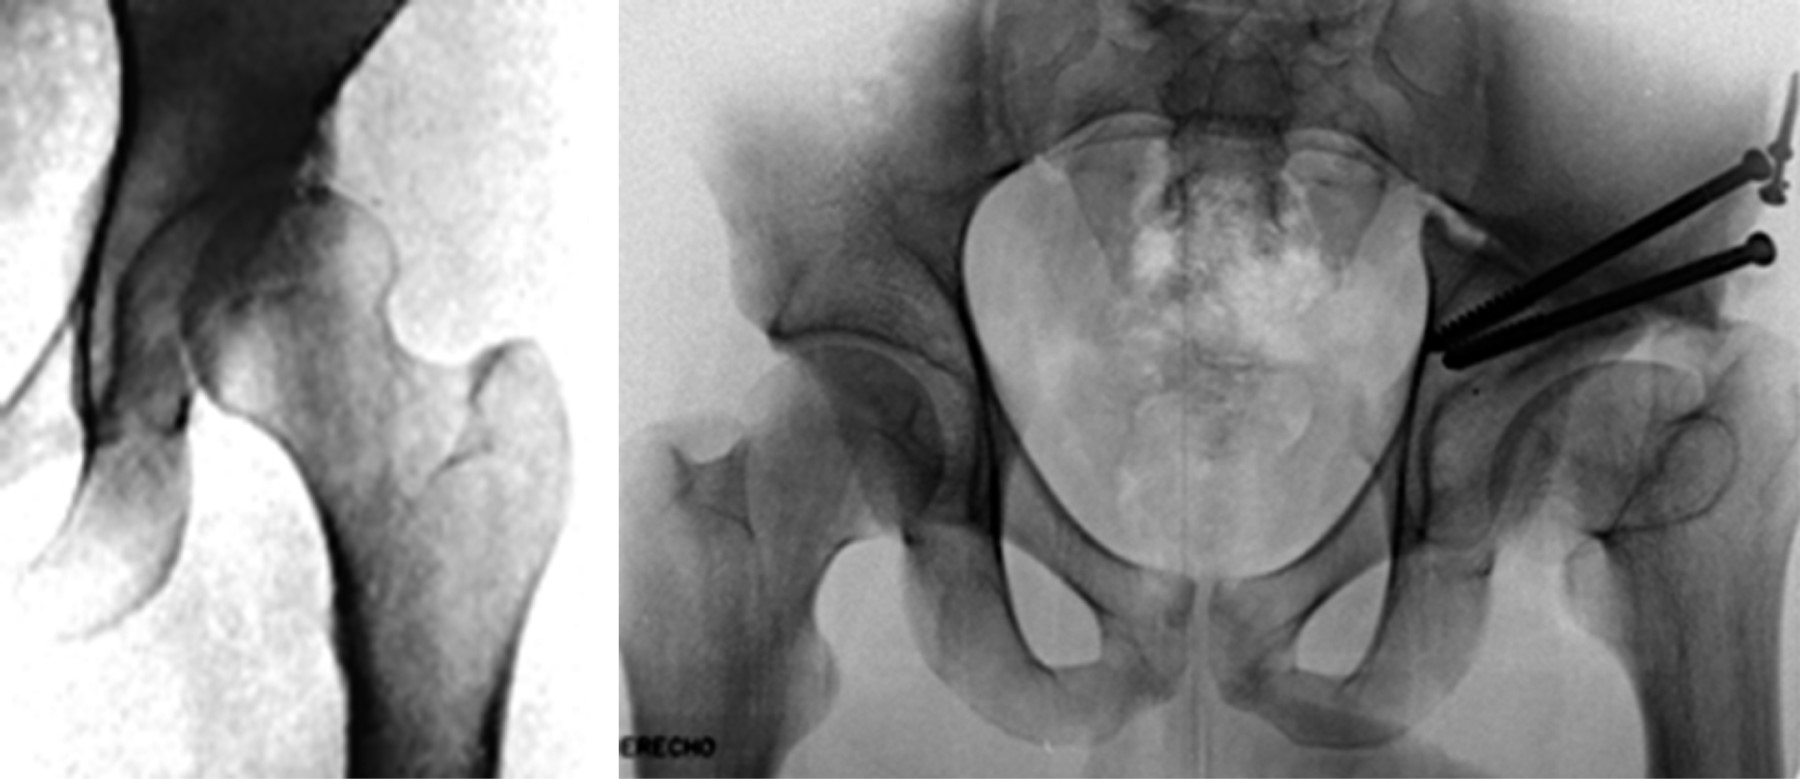

Osteotomías pélvicas

Las osteotomías pélvicas fueron ideadas principalmente para resolver el grave problema de las secuelas de una luxación congénita de la cadera no tratada o insuficientemente tratada. Han sido varios los autores que han contribuido con su experiencia y talento ideando diversos tipos de osteotomías (Figuras 3 y 4). El objetivo de éstas es reorientar el acetábulo en relación con la cabeza femoral, proporcionando cobertura y contención adecuada a la cabeza del fémur.

El pionero del tratamiento con osteotomías pélvicas fue Robert Bruce Salter,24 quien en 1961 hacía un corte de osteotomía supraacetabular en cuña en niños e introducía en ella un injerto óseo autólogo tomado de la cresta ilíaca para mantener la posición del acetábulo reorientado. Se usa como fulcro la sínfisis púbica.

La idea de reorientación acetabular de Salter fue seguida por diversos autores. David Hollingworth Sutherland25 en 1977 modificó la técnica de Salter al agregar al tradicional corte supraacetabular en ilíaco una osteotomía adicional cerca de la sínfisis del pubis. Llamó a esta técnica "doble osteotomía innominada".

Después de la innovación de Sutherland, quien propuso una doble osteotomía, Howard H. Steel26 siguió el mismo principio, pero lo hizo efectuando una triple osteotomía, osteotomizando el ilíaco, el isquion y el pubis separadamente. A esta técnica la llamó "triple osteotomía innominada". Esto ocurrió en 1973 (Figura 5).

Más tarde en 1981, Dietrich Tönnis27 hizo modificaciones a la técnica de triple osteotomía de Steel, proponiendo que los cortes de osteotomía no deben hacerse alejados de la articulación, sino por el contrario, lo más cerca posible. Con esta modificación buscó disminuir la limitante en la movilización del fragmento acetabular, que era ocasionada por los tejidos blandos que actúan como una brida dificultando su movilización, como ocurría con las osteotomías de Sutherland y Steel. La llamó "triple osteotomía yuxtaarticular" (Figura 6).

Desafortunadamente, en las osteotomías anteriores que cortan el hueso innominado en diferentes partes, ya sea cerca o lejos de la articulación, los tejidos blandos que se insertan rodeando el acetábulo actúan como una auténtica correa o brida que limita el grado de corrección deseada y pueden llevar a inestabilidad del fragmento acetabular libre. Otro problema es que irrumpen la columna y muro posterior desfigurando el anillo pélvico. La gran limitante de estas osteotomías (a excepción de las periacetabulares que trataremos más adelante) es que están diseñadas para efectuarse principalmente en niños, ya que éstos tienen los centros de cartílago de crecimiento abiertos en el cartílago trirradiado. Aunque se han intentado en adultos, sus resultados a largo plazo no son los esperados. Basta con mencionar a Peters28 y colaboradores, quienes siguieron a 50 pacientes adultos por un período de nueve años que habían sido osteotomizados con la técnica de Steel y encontraron una tasa de falla de 27%.

En 1955 Karl Chiari29 ideó una osteotomía que tiene un concepto totalmente diferente al resto de las osteotomías existentes en esa época para el tratamiento de la displasia acetabular. El procedimiento consiste en efectuar una osteotomía ilíaca supraacetabular completa, que permita el desplazamiento el fragmento inferior (trasfondo-cabeza) medialmente y el superior lateralmente. Esto produce una disminución del brazo de palanca medial y un aumento en la cobertura a la cabeza femoral por el fragmento ilíaco superior. El resto de la pelvis queda en su lugar de origen (Figura 7). El requisito indispensable es interponer la cápsula articular entre el fragmento superior desplazado y la cabeza femoral, la cual sufriría una metaplasia a fibrocartílago. Aunque desfigura el anillo pélvico, esta osteotomía fue muy popular, ya que técnicamente es muy fácil de hacer; sin embargo, con la aparición de las osteotomías periacetabulares y las prótesis de cadera prácticamente se ha abandonado.

Un hito en el tratamiento de la displasia acetabular en adultos con osteotomías fue el desarrollo de las osteotomías periacetabulares sin irrupción del anillo pélvico; los máximos representantes en este tipo de osteotomías fueron Heins Wagner30 y Reynold Ganz.31

Wagner30 en 1978 contribuyó de manera importante a este concepto con su osteotomía esférica periacetabular. Las osteotomías periacetabulares en general tienen la enorme ventaja de que no irrumpen la columna ni el muro posterior, dejando intacto el anillo pélvico. Por lo anterior, es mucho mejor la estabilidad que se obtiene en el fragmento libre acetabular osteotomizado. Otra ventaja es que se facilita el grado de cobertura de la cabeza femoral, y ya no se tiene la limitación de la movilización del fragmento acetabular al no intervenir de manera importante los tejidos blandos. Por lo anterior, se pueden obtener mucho mejores correcciones.

Sin duda, el que más contribuyó a la idea de las osteotomías periacetabulares fue Reynold Ganz,31 quien describió una osteotomía periacetabular que nombró "osteotomía bernesa" (Figuras 4 y 8). A esta osteotomía se le considera en la actualidad el estándar de oro para corregir las secuelas de las displasias acetabulares. Desafortunadamente, no es de utilidad cuando se aplica en casos avanzados de coxartrosis.